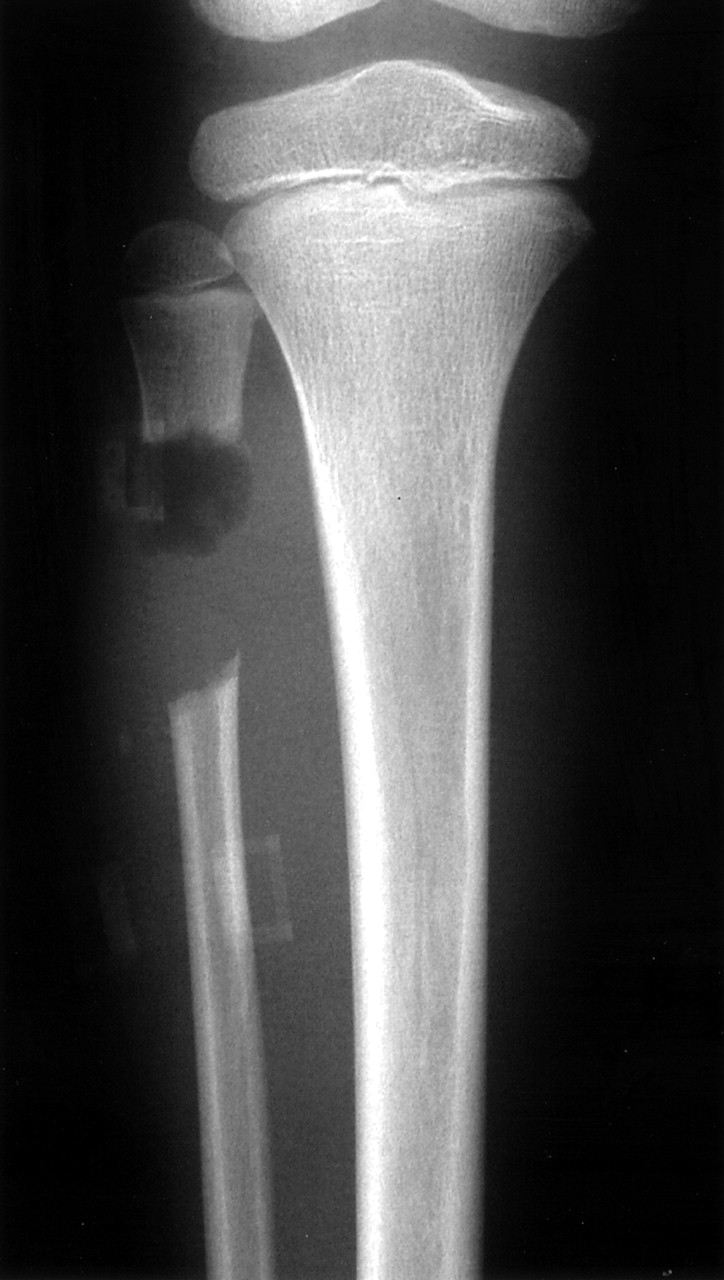

Μέσω της λαπαρασκόπησης εισάγεται στο τραύμα ένας μικρός συνδετήρας που λειτουργεί ως στήριγμα των τραυματισμένων συνδέσμων ή αρθρώσεων.

Ο συνδετήρας αυτός επιτρέπει στον ασθενή να κινείται και παράλληλα υποστηρίζει τους συνδέσμους μέχρι να επανέλθουν.

Η τεχνική αυτή έχει δοκιμαστεί σε περίπου 20 ασθενείς κι έχει παρατηρηθεί ταχύτερη ανάρρωση και λιγότερη δυσφορία, ενώ φαίνεται ιδιαίτερα ελκυστική στους αθλητές που δεν μπορούν να μείνουν για μεγάλο χρονικό διάστημα μακριά από τους στίβους.